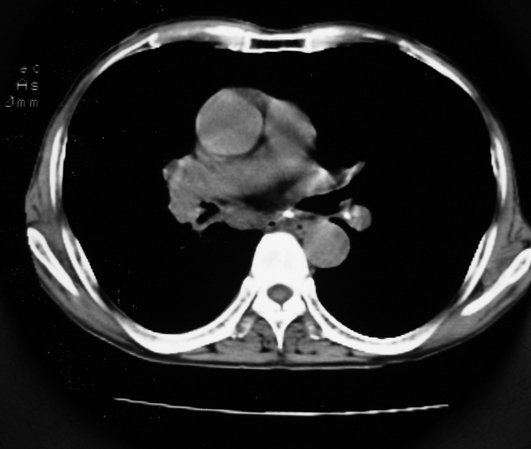

以下是引用同在2007-1-27 14:13:00的发言:[br]支持右侧中央型肺癌伴阻塞性病变.

以下是引用zjzjr在2007-1-27 16:56:00的发言:[br]支持右肺中心型肺癌伴阻塞性肺炎.